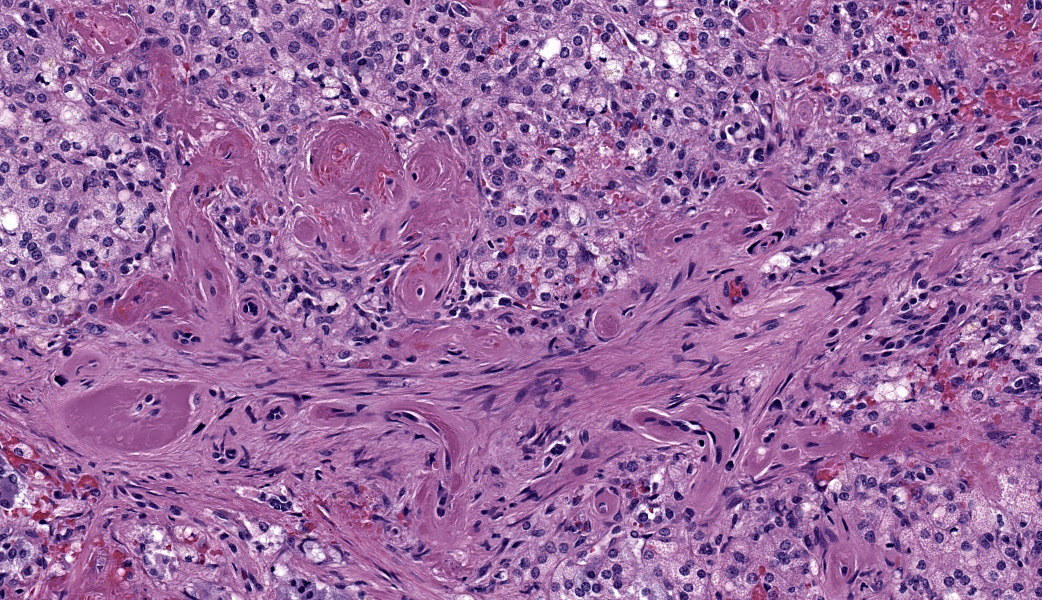

Adrenal glands: Multifocally, the small arteries and arterioles within the cortex and medulla show marked thickening of their walls, and narrowing or obliteration of their lumen, by intramural deposition of plasma proteins (consistent with hyaline arteriolosclerosis). Some vessels show intramural laminar deposits of plasma proteins (onion-skinning). Many sinusoidal vessels in the medulla are occluded by fibrin thrombi and are frequently effaced by hyaline material.Contributor's Morphologic Diagnoses:

Adrenal glands: Multifocal hyaline arteriolosclerosis.Condition: Hypertensive vasculopathy. Other diagnoses (tissues not included in the submission):

Adrenal gland, arterioles: Fibrinoid necrosis, chronic, diffuse, moderate, with fibrin thrombi and hemorrhage.JPC Comment:

So, what about arteriolosclerosis? How does that compare to arteriosclerosis? Arteriosclerosis usually affects large arteries, such as the abdominal aorta in horses, ruminants, and carnivores, and is an aging change. Arteriolosclerosis affects small arterioles and is largely due to endothelial damage secondary to hypertension. There are two types of arteriolosclerosis: hyaline and hyperplastic. The hyaline form is considered the acute stage. In the hyperplastic form, proliferation of smooth muscle cells within the tunica intima, coupled with concentric fibrosis, can lead to a characteristic ?onion-skinning? appearance of the affected vessels with chronicity.

Wrapping up conference discussion was a review of primary vs. secondary hypertension, which the contributor did an excellent job of covering in their comment. Hypertension causes hyaline arteriolosclerosis by causing endothelial damage, which then forces serum proteins from the blood out into the arteriolar walls where they accumulate and form deposits. This is traditionally referred to as ?fibrinoid necrosis?, and conference participants elected to use this term for the morphologic diagnosis. Additionally, the damage to the vessel walls from the increased pressure causes them to become tortuous and stimulates them to thicken and harden via smooth muscle proliferation and fibrosis as previously mentioned, reducing their elasticity and narrowing the lumen. This impairs blood flow and may result in thrombosis.3 In cases of hypertension, the most common presenting clinical sign in affected animals is acute blindness secondary to hypertensive retinopathy.